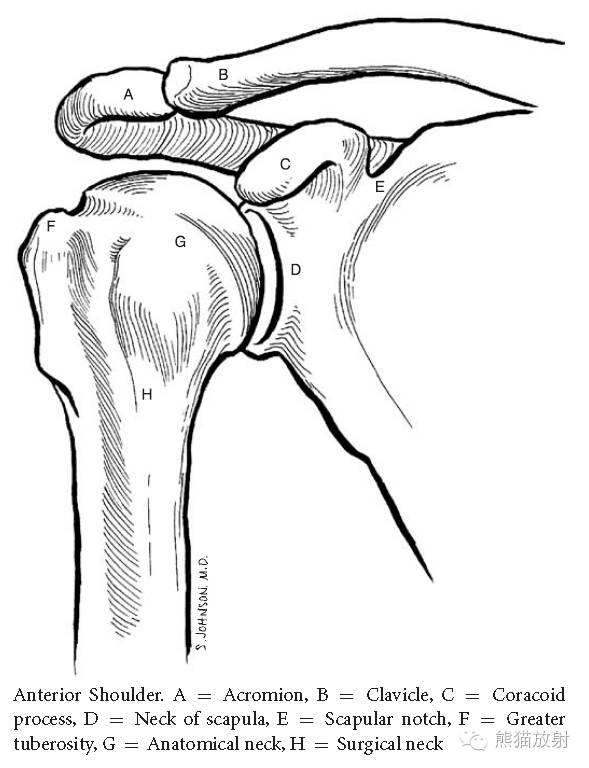

肩关节正常解剖

肩关节正位:A=肩峰,B=锁骨,C=喙突,D=肩胛颈,E=肩胛切迹,F=肱骨大结节,G=解剖颈,H=外科颈。